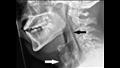

ومع ذلك، في هذه الحالة بالذات، انتهى الأمر بالمريض إلى تمزق 2 ملم في القصبة الهوائية، ما تسبب في ألم شديد.

وتمزق الحلق، المعروف طبيًا باسم "الثقب الرغامي التلقائي"، هو إصابة نادرة وربما تهدد الحياة ولم تكن مرتبطة بالعطس الخانق من قبل.

وعندما وصل الرجل إلى غرفة الطوارئ، كان يعاني من آلام شديدة، وكانت رقبته متورمة من الجانبين وبالكاد يستطيع تحريك رأسه.

وأثناء فحص المريض، تمكن الأطباء من سماع صوت طقطقة من داخل حلقه، ما يشير إلى أن هناك شيئًا ما ليس على ما يرام، ولم تتداخل الحالة مع التنفس أو البلع أو التحدث.